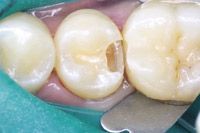

The caries were carefully excavated resulting in a deep preparation, especially on the axial wall (Fig. 3).

Fig. 3